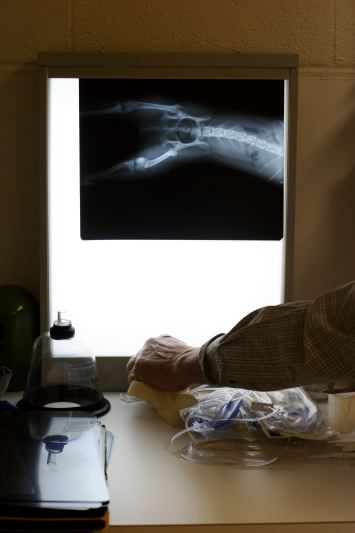

Madinsonville Veterinary Clinic

by Ashley Wilkerson

Dr. Slaton jokes with customers during a busy day at the Madinsonville Veterinary Clinic on Friday, October 20, 2006. While he spends most of his time tending to the animals, filling prescriptions and completing paperwork, he enjoys the few moments to interact with the pet owners, many with whom he is long-time friends.